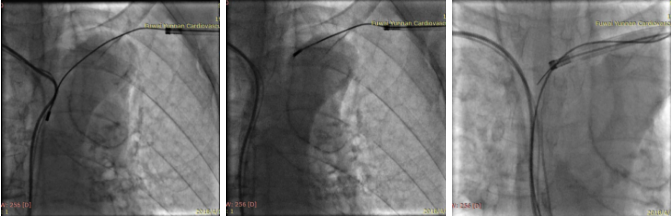

A、B为拔除心房电极X影像,C为拔除心室电极X影像